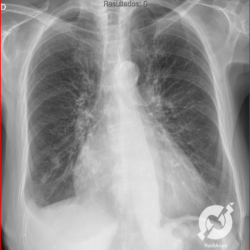

Aumento do volume cardíaco, inversão da circulação pulmonar, lesões intersticiais reticulares e obliteração do seio costofrênico direito.